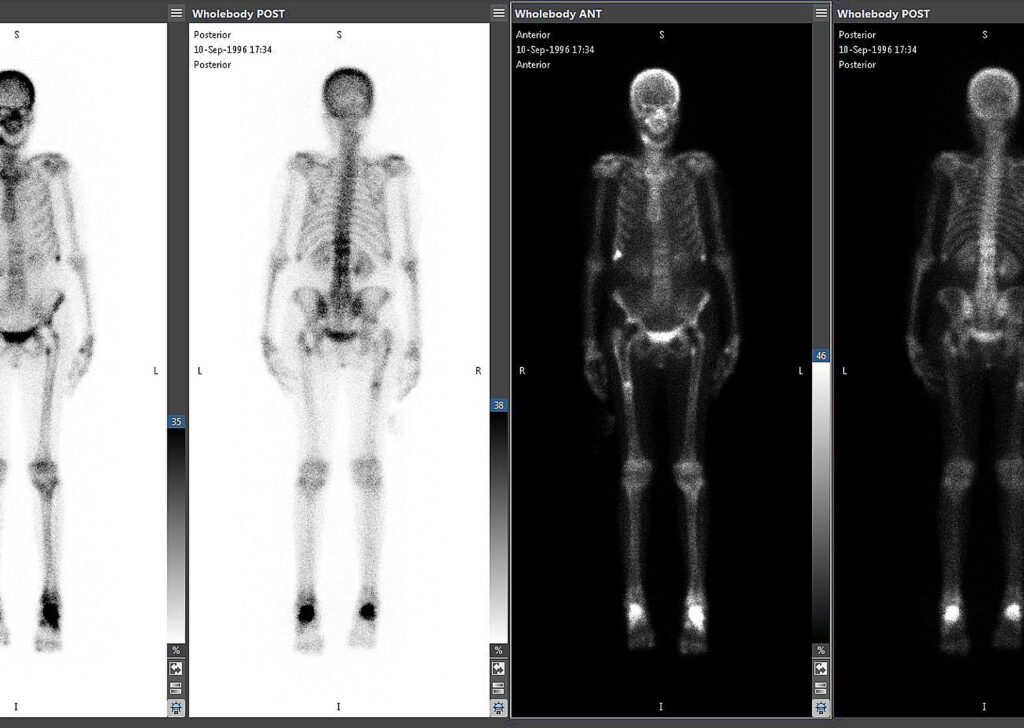

Mirada Nuclear Medicine

Mirada Nuclear Medicine (NM) is integrated into Vitrea Advanced Visualization. Flexible display protocols and workflows allow quick and easy reading of Nuclear Medicine studies.